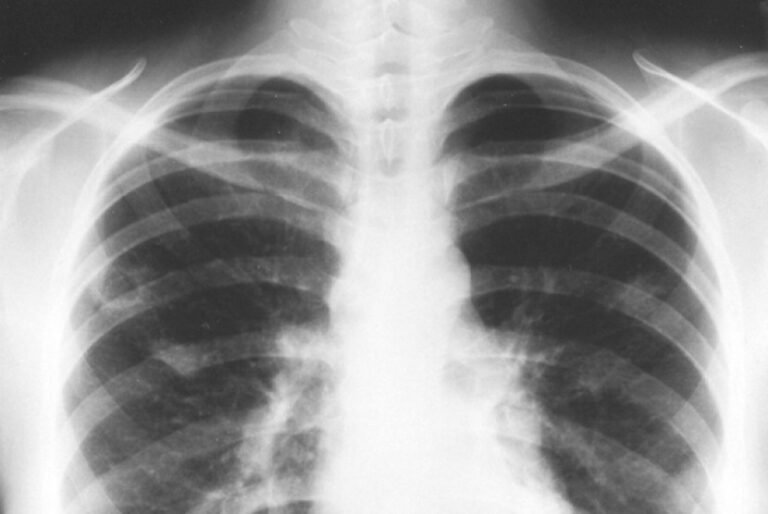

Secara klinis, ciri ciri flek paru paru biasanya muncul sebagai keluhan pada saluran pernapasan dan kondisi umum tubuh. Keluhan-keluhan ini tidak spesifik hanya untuk satu penyakit, tetapi sering ditemukan pada orang yang kemudian pada pemeriksaan menunjukkan adanya flek di paru paru.

Singkatnya, ciri ciri flek paru paru umumnya berupa kombinasi batuk lama, sesak, nyeri dada, mudah lelah, demam ringan berulang, serta penurunan berat badan dan nafsu makan. Ciri ciri ini menggambarkan adanya gangguan pada paru yang perlu diperhatikan dengan saksama.